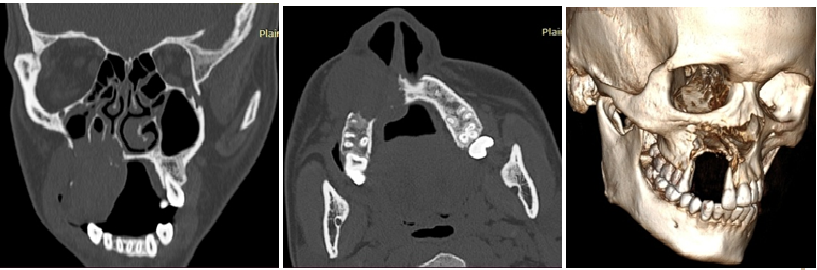

CT Scan of the face showed an expanding, well-defined, destructive lytic lesion (3.6x3.5x4.2cm) involving alveolar and palatine process of right maxilla and anterior & medial walls of right maxillary sinus, right gingivo-buccal complex, part of right buccinator muscle and the right nasolabial fold with bone destruction. In addition, bony nasal septum was slightly deviated towards the right. The radiological findings were consistent with a neoplastic etiology ([Figure 3]).